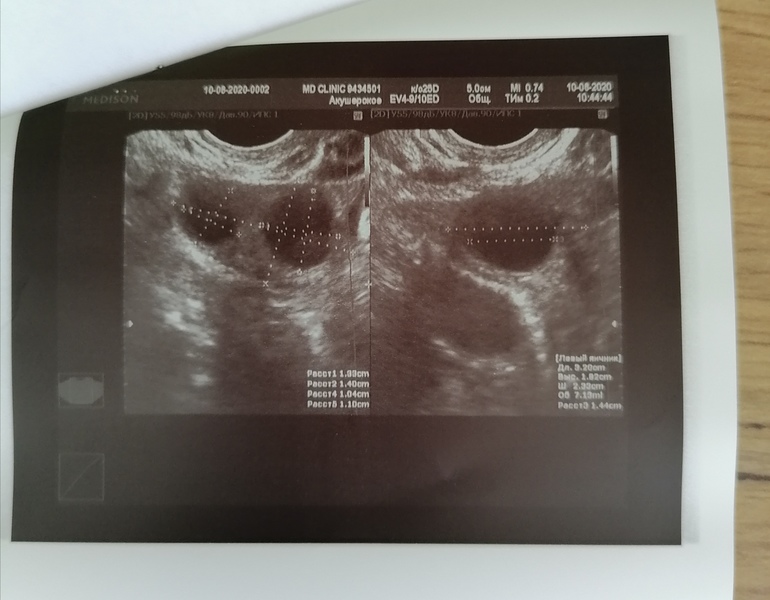

Сходила сегодня на узи к своему врачу у которой веду все беременности. Вообщем у меня 3 ДФ на 6 ДЦ. Овуляция будет ранняя однозначно. Надо теперь наростить эндометрий и вперёд. Пойду ещё на 11 ДЦ.

Это левый яичник с 2мя фоликами

Совершенно точно это не ЖТ и не кисты. Включали и кровоток смотрели.